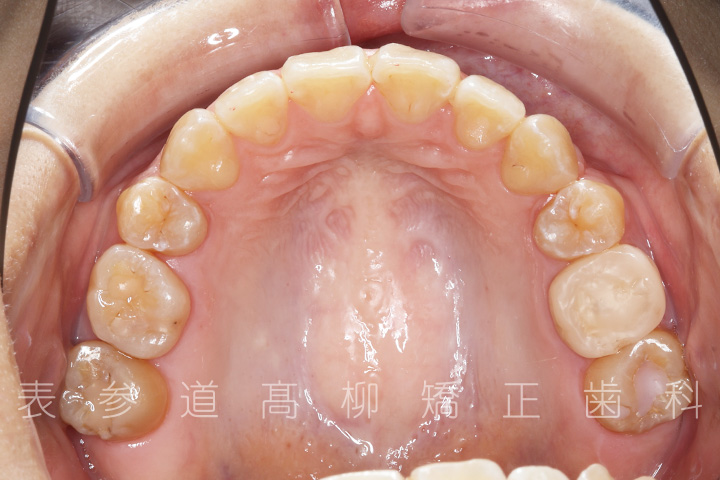

前歯のガタガタ感と開咬でお悩みの患者様の症例をご紹介いたします。

・前歯部開咬

・上下前歯部叢生(凸凹歯並び)